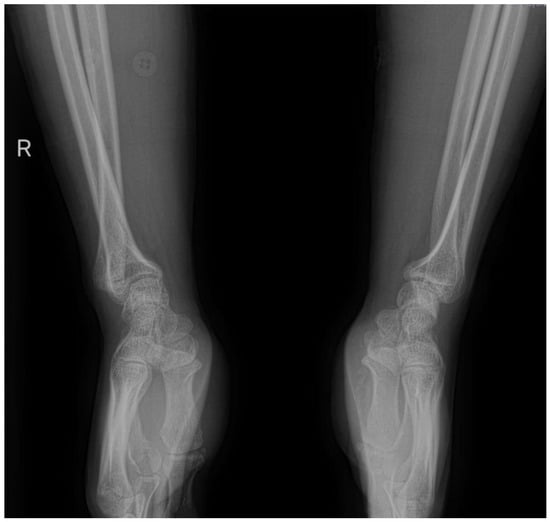

5.1. Conventional Radiography

Conventional radiography is valuable for evaluating joint instability and excluding other potential causes of wrist pain, such as fractures or arthritis [12]. However, it primarily focuses on bone imaging and may not fully assess soft tissue structures, although sometimes, DRUJ injuries can be seen via simple X-ray, as illustrated in Figure 1, which shows a forearm fracture with an associated DRUJ injury (there is an increased radioulnar distance, as well as a dorsal dislocation of the ulnar head) (Figure 2). Dynamic joint motion cannot be evaluated with static radiographic images. In cases of suspected ligamentous injuries or more complex DRUJ pathology, additional imaging modalities like MRI or CT may be necessary for a comprehensive assessment [25,26].

Figure 2. Forearm fracture with radiographic evidence indicating distal radioulnar joint (DRUJ) injury: (a) antero-posterior view (increased radioulnar space); (b) lateral view (dorsal dislocation of the ulnar head).